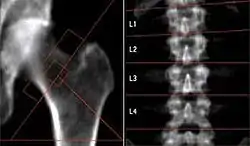

The image on the right shows the loss of bone mass apparently due to long-term microgravity on the International Space Station. "[A]stronauts, on average, lost roughly 11 percent of their total hip bone mass over the course of their mission."[4]